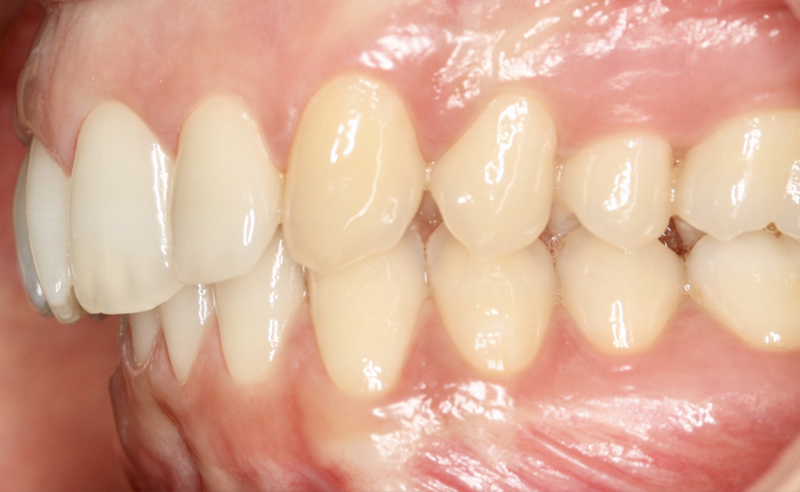

Fotografe a sua Boca de acordo com os exemplos abaixo demonstrados